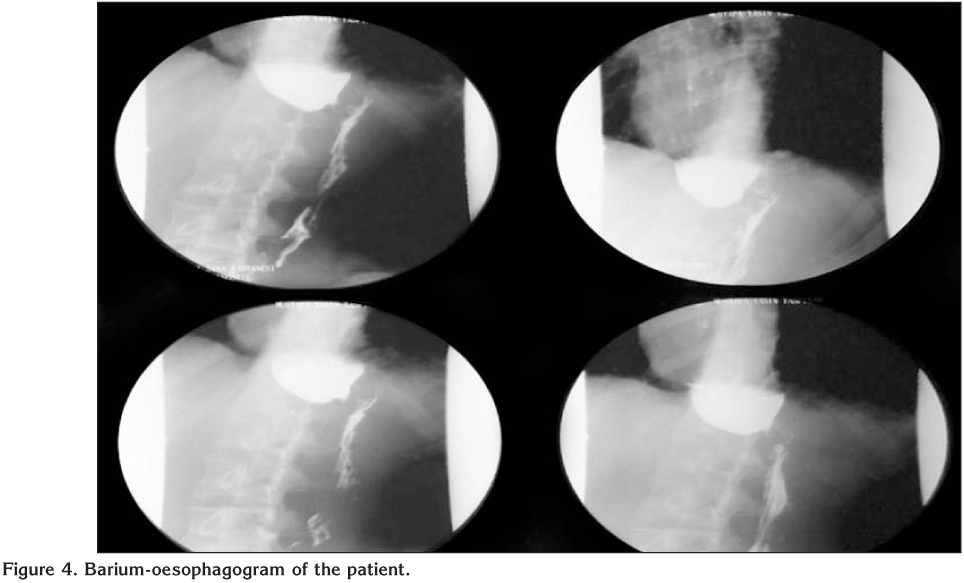

An 18-years-old male patient applied to a clinic with the complaints of cough, dyspnea, wheezing and diagnosed as asthma. A fluticasone/salmeterol combination inhaler therapy was prescribed. While he did not recover, inhaled steroid dosage was increased and montelukast was given as add-on-therapy. The patient was referred to our hospital with difficult asthma diagnosis. He reported cough increasing at night, regurgitation and dyspnea while eating. Spirometry revealed a non-reversible airway obstruction (Figure 1A). On chest X-ray there was a mild upper mediastinal enlargement (Figure 2A). Chest computed tomography revealed an over-dilated oesophagus constricting the trachea (Figure 3). The patient was referred to chest surgery clinic with a suspected diagnosis of achalasia. A clear narrowing of oesophagus at the oesophagogastric junction was seen in barium-oesophagogram (Figure 4). Oral intake was stopped and 3000 cc fluid was aspired with nasogastric tube. Endoscopic evaluation of the oesophagus revealed an increased pressure on lower oesophageal sphincter, dilated oesophagus without peristaltism. After left thoracotomy, increased pressure on lower oesophageal sphincter and dilated oesophagus was explored. The patient underwent Heller myotomy and oesophagogastrostomy. He was recovered in one week after the surgery without any complaint of dyspnea. Spirometry tests and chest X-ray resulted normal in one year (Figures 1B,1C,1D and Figure 2B).

Figure 4